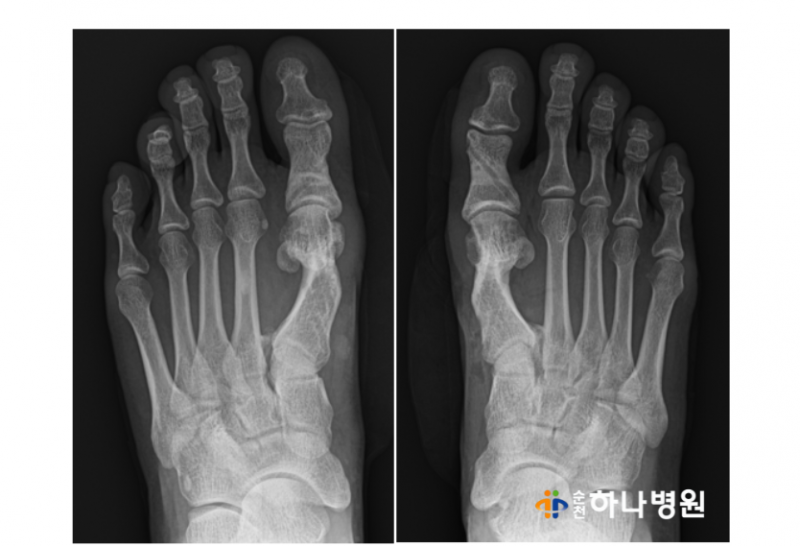

x-ray와 각도를 확인 한 결과

우측 ( 무지외반각도 31' / 제1-2 중족골간각도 16' )

좌측 ( 무지외반각도 25' / 제1-2 중족골간각도 16' )

양쪽 모두 '중등도 변형'을 나타내고 있는 상태!!

사진 상으로 양측 모두 엄지발가락이 두번째 발가락을

밀어 내고 있고, 제 1중족골두가 툭 튀어 나와있는 모습이

뚜렷했습니다.

무지외반증 수술 후 각도 확인 결과

우측 ( 무지외반각도 31' / 제 1-2중족골간각도 16')

→ (무지외반각도 9' / 제1-2중족골간각도 7')

좌측 (무지외반각도 25' / 제1-2 중족골간각도 16')

→ (무지외반각도 9' / 제1-2 중족골간각도 8')

모두 중등도 변형에서 '정상'으로 회복된 모습을

확인할 수 있습니다.

사진에서도 보시다시피

양측 모두 엄지발가락 2번째 발가락을 밀지 않고

평행한 모습을 보실 수 있습니다^^

제1중족골두가 툭 뒤어 나와있던

부분 또한 없어진 모습!